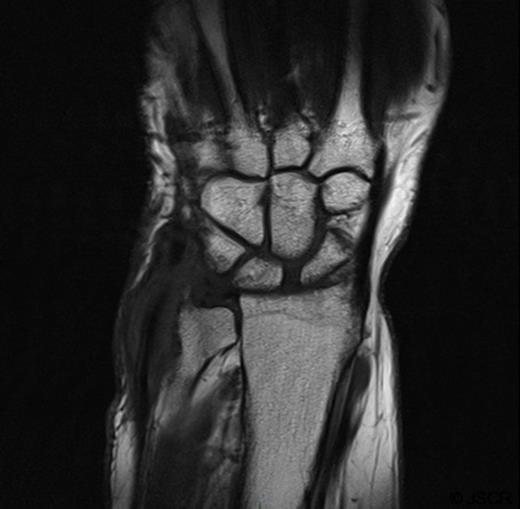

She was subsequently referred to the hand clinic. X ray this time showed destruction of the ulnar styloid consistent with a bony infection (Figure 2). MRI showed destruction localised around the ulnar head with oedematous changes extending up the shaft of the ulna (Figure 3).

MRI showing localised destruction around the ulnar head. The MRI also shows thickening around the extensor carpi ulnaris tendon in keeping with marked tenosynovitis at this site.